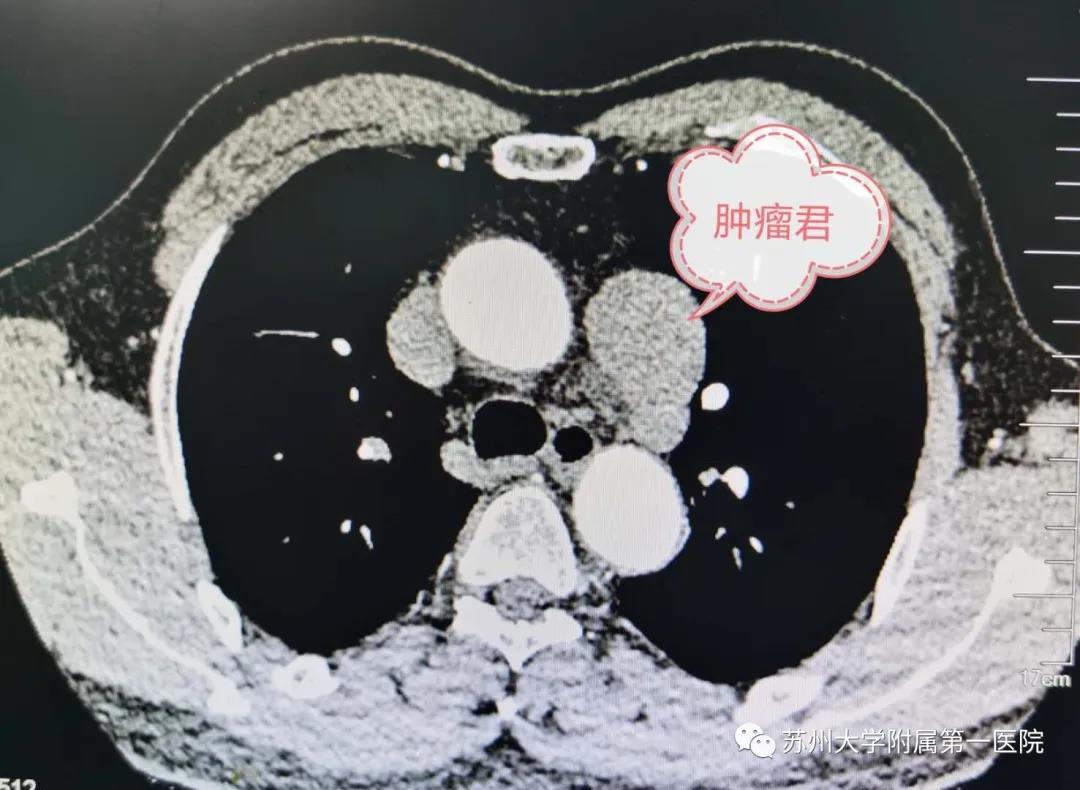

“神队友”奥利给!苏大附一院胸外科团队与机器人携手完成肿瘤切除...

“神队友”奥利给!苏大附一院胸外科团队与机器人携手完成肿瘤切除...